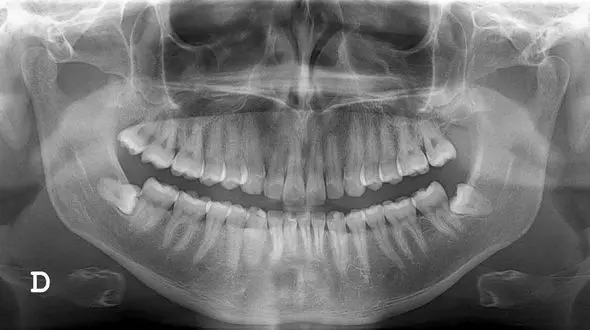

رکنا : عکس OPG برای بررسی وضعیت دندان ها از سوی دندانپزشک

سلامت رکنا : دندان های عقل بالاترین شیوع نهفتگی را دارند و علت آن تغییر رژیم غذایی انسانها در طول سال هاست.